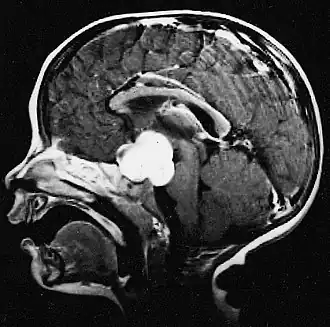

![]() Imagen de RM de un astrocitoma pilocítico en la región hipotalámica | ||

Este tumor se presenta generalmente como una lesión circunscrita y bien delimitada, de crecimiento lento y puede ser sólido o quístico.[2] Suelen apreciarse con facilidad en las imágenes de TC y RM. Los quistes pueden ser monoloculares o multiloculares, con el nódulo tumoral encapsulado en el interior. El astrocitoma pilocítico generalmente aparece a nivel del cerebelo, tronco cerebral, región hipotalámica, nervios y quiasma óptico, y en general en cualquier área donde haya presencia de astrocitos, incluyendo los hemisferios cerebrales y la médula espinal. La localización más frecuente es el cerebelo.[3]